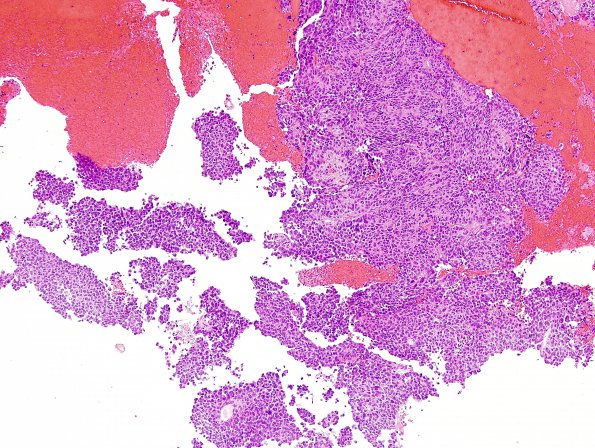

Washington University Experience | NEOPLASMS (PINEAL) | Papillary Tumor Pineal Region (PTPR) | 10A1 Papillary Tumor Pineal Region (Case 10) H&E 4.jpg

Case 10 History ---- The patient is a 73 year old woman with a tumor in the posterior part of third ventricle/pineal region. Systemic workup for another primary was negative. Operative procedure: Partial excision. ---- 10A1,2 Sections reveal a solid-appearing epithelioid neoplasm with prominent papillary growth pattern. There is moderate to marked nuclear pleomorphism with tumor cells displaying anaplastic features. The tumor cells are large and epithelioid with moderate quantities of eosinophilic cytoplasm and large hyperchromatic oval to irregular nuclei. The mitotic index is elevated and there are atypical mitoses. Small foci of tumor necrosis are also evident. Occasional intracytoplasmic clear vacuoles are seen.